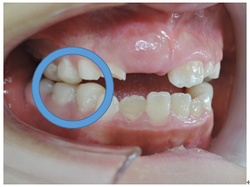

初診時乳臼歯にレジンを盛る事で咬み合わせの高さを治療していきます。

乳臼歯にレジンを盛る事で第一大臼歯の咬み合わせに隙間が出来ました。

約2か月で隙間が埋まり第一大臼歯が咬み合いました。

上顎から矯正装置を装着していきます。